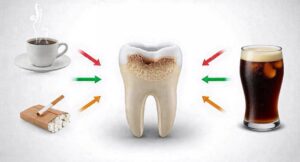

Žuti zubi – kako nastaju i kako da postanu belji

октобар 30, 2025

Erozija zuba – kako nastaje i kako sačuvati osmeh

октобар 10, 2025